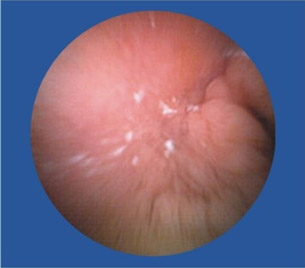

口服后借助消化道蠕动使之在消化道内运动,从食道→胃→十二指肠→小肠→结肠→直肠的方向运行探测,胶囊内的摄像头像卫星扫描技术一样, 对经过的腔段进行连续摄像,以每秒两幅图像的拍摄频率,通过电磁信号被无线传输到病人随身携带的数码记录仪上。

OMOM胶囊内镜数码相机工作结束后,医生即可取下数据记录仪与影像工作站连接,下载数万张图像数据,能有效诊断整个消化道疾病, 更能探测到被称为胃肠检查盲区的“小肠”。在无线胶囊吞服8~24小时后,就会由患者的肠道自动安全排除体外。

便血,去做检查,痔疮、胃镜、纤维结肠镜都做后,的出结论——小肠流血,但结肠镜够不着,还是看不见在具体位置。因此,也算是体验了下高科技,胶囊内镜。试过后真是感叹,这玩意儿真厉害!比普通药丸子稍大,一喝水下去了。自动掉头,自动拍照,自动传输。拉出来后找护士要了些消毒药水洗了下,细细观察。发现镜头口径有点小最多1mm,确实是高科技,这么小的东西,包括了拍照(可能是2个小时内的连续拍照),无线信号传输,方向姿势控制等等,厉害。

近日,67岁的陈爷爷因为便血导致严重贫血,胃镜、肠镜都做了却查不出病因。被转送到四川肛肠医院后,陈爷爷本来以为要再接受一次痛苦的内镜检查,没想到,医生给出的检查方式却是要他吞下一颗“胶囊”,同时穿上一件连着各种数据线的背心。很快,医生就发现陈爷爷的小肠上面存在一个不断出血的溃疡,经过手术,医生终于治好了陈爷爷的“怪病”。陈爷爷吞下的其实是一种叫“OMOM胶囊内镜”的检查仪器,主要用于小肠疾病的排查。